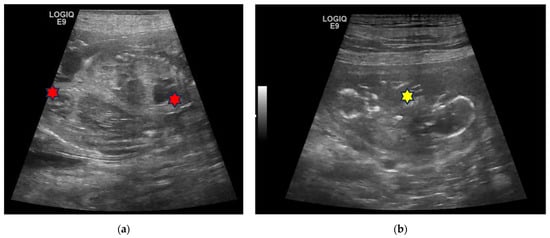

| 4C | 5-year-old Labrador Retriever female dog | 25, 32, 39, 46 and 53 | 10 | Monochorionic twins, morphologically comparable to the other embryos/foetuses. | C-section. Twins of different sex, alive, with partial twisting of the umbilical cord. One stillborn, two puppies euthanatized for malformations. | Death of the male twin after 7 days of hypoglycaemia and dehydration. |

| 5C | 3-year-old Australian Shepherd female dog | 23, 30, 37, 44 and 51 | 12 | Monochorionic twins, morphologically comparable to the other embryos/foetuses. | Natural delivery, dystocia, C-section. Ten puppies alive and two dead twins of the opposite sex. | |